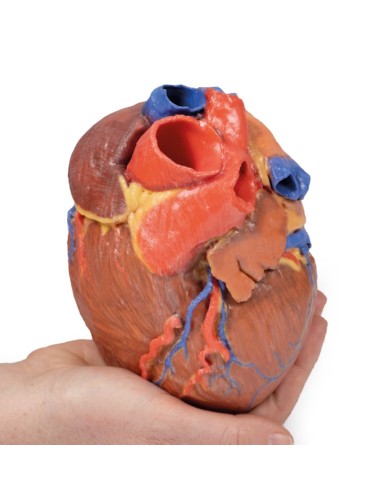

Modello di cuore di alta qualità scomponibile in 5 parti

Modello di cuore di alta qualità scomponibile in 5 parti

La parete anteriore del cuore è staccabile per poter vedere i ventricoli.

Realizzato in stampa 3D ad elevatissima risoluzione a colori.